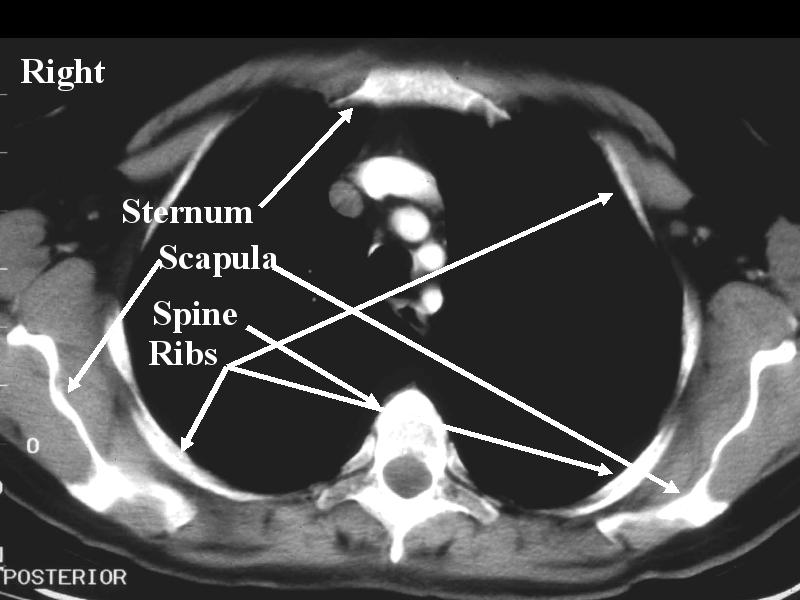

MS 156 CT NL 54